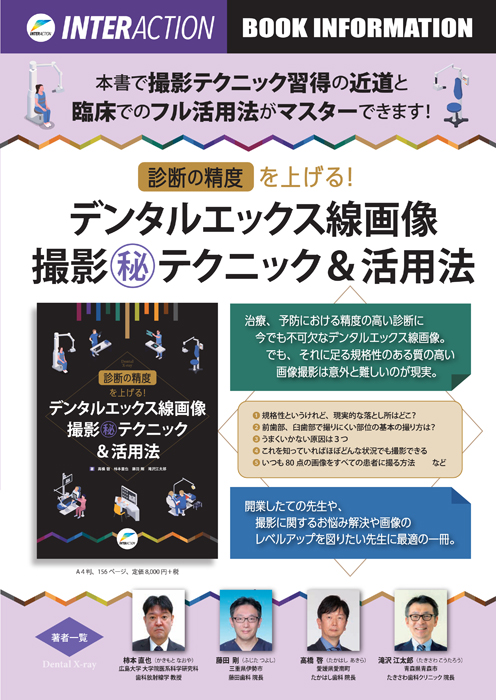

診断の精度を上げる!デンタルエックス線画像撮影㊙テクニック&活用法 | 柿本 直也, 藤田 剛, 高橋 啓, 滝沢 江太郎 |本 | 通販 | Amazon

『診断の精度を上げる!デンタルエックス線画像撮影㊙テクニック&活用法 | 柿本 直也, 藤田 剛, 高橋 啓, 滝沢 江太郎 |本 | 通販 | Amazon』はセカイモンでec19cb76から出品され、192の入札を集めて05月07日 12時 48分に、6800円で落札されました。即決価格は6800円でした。決済方法はに対応。海外からの発送料は落札者が負担しました。PRオプションはストア、取りナビ(ベータ版)を利用したオークション、即買でした。

診断の精度を上げる!デンタルエックス線画像撮影㊙テクニック&活用法 | 柿本 直也, 藤田 剛, 高橋 啓, 滝沢 江太郎 |本 | 通販 | Amazon,書籍詳細「診断の精度を上げる! デンタルエックス線画像撮影㊙テクニック&活用法」 | フォルディネット,書籍詳細「診断の精度を上げる! デンタルエックス線画像撮影㊙テクニック&活用法」 | フォルディネット,第3回 X線動態画像セミナー(WEB配信) - ヘルスケア | コニカミノルタ,楽天ブックス: 診断の精度を上げる!デンタルエックス線画像撮影(秘)テクニック&活用法 - 高橋啓 - 9784909066671 : 本